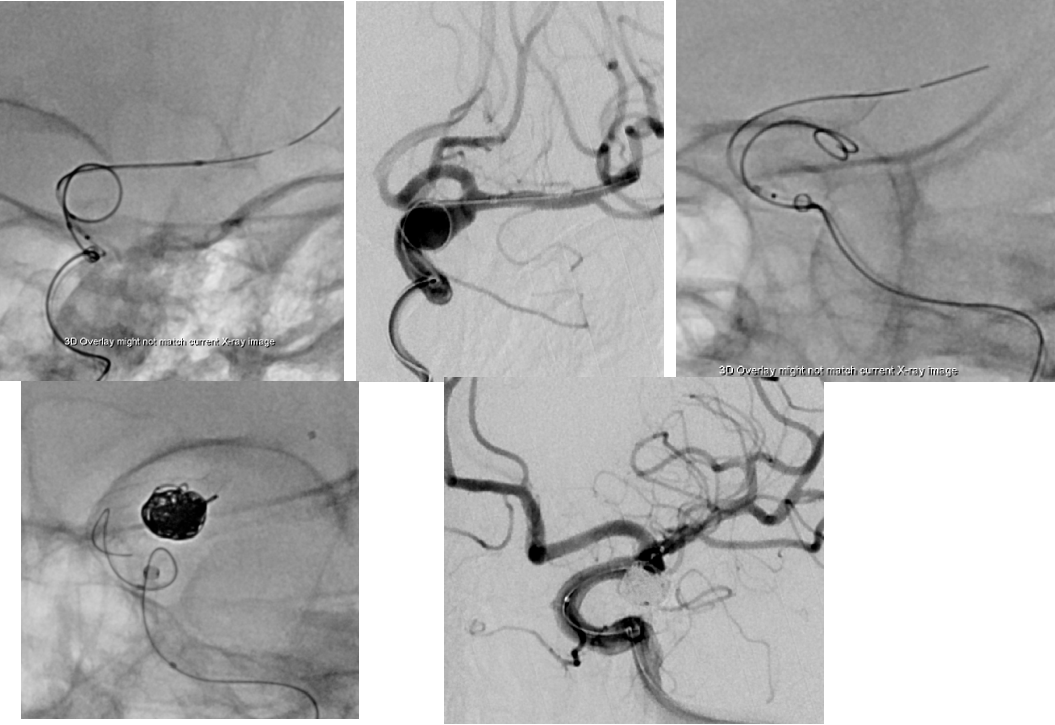

造影检查,备颅内动脉瘤栓塞术+nuva 密网支架植入

2023-05-11 手术

选择TJED5.0-18(4.5x27),泰杰18微导管,支架输送费劲,维持张力释放自膨好,没有疝入动脉瘤,支撑力好;转弯处稍减张释放,支架尾端没打开;推拉支架导丝,尾端打开;过管顺利,填圈。

术后即刻DSA

手术过程

手术材料

通路:8F指引导管、 Navien 072-115中间导管

微导管微导丝:Echelon10微导管,Synchro-14微导丝,泰杰微导管

弹簧圈:泰杰7mm*30cm 3D、泰杰6mm*15cm 3D、泰杰4.5mm*12cm 3D

支架:Nuva血流导向密网支架TJED-D-5.0-18(4.5x27)

封堵系统:动脉缝合器、压迫器